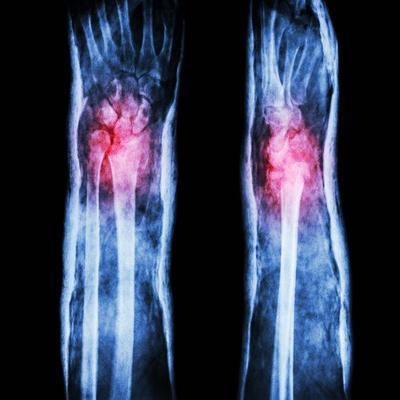

1.影像学检查:患者可以通过MRI、CT等方法来检查,MRI也叫做核磁共振,原理是通过对静磁场中的人体施加某种特定频率的射频脉冲,然后再使人体中的氢质子受到激励所发生的磁共振现象。脉冲结束后,质子在弛豫过程中还会产生MR信号。人体再通过MR信号的接受、空间编码,或者图像的重建等方法处理的过程来产生MR的信号。CT的原理是利用精准准确的X线束或者超声波等方法来确诊。